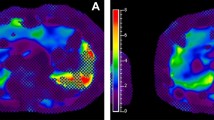

Liver iron overload can occur in conditions such as primary hemochromatosis, transfusional hemosiderosis in children with sickle cell hemoglobinopathies, thalassemia, and in chronic liver diseases. Severe iron overload can lead to cellular damage and diminished organ function in the liver and heart. Thus methods to accurately quantify liver iron deposition are important to allow for appropriate clinical management. While non-targeted percutaneous liver biopsy and estimation of liver iron concentration (LIC) is the gold standard method of liver iron quantification, biopsy does have limitations because of its invasiveness and sampling variability [53]. MRI is a very commonly used noninvasive method of liver iron quantification because of its availability and lack of ionizing radiation. The MRI methods include signal intensity ratio techniques using T2- or T2*-weighted images, R2 (1/T2) and R2* (1/T2*) relaxometry techniques, and MR susceptometry.

The R2 relaxometry technique uses a series of single spin echoes (SSE), each acquired after a separate excitation, or by using a train of spin echoes following a single excitation using a Carr–Purcell–Meiboom–Gill sequence [55]. The echo times used typically range from <5 ms to 15–30 ms. R2 can be estimated by plotting the decay of signal intensity values with TE as a mono-exponential or bi-exponential decay. The main limitation of the R2 relaxometry method is the long acquisition time required for R2 mapping by using SSE image sequences. The St. Pierre method is the most popular R2 relaxometry technique based on the non-linear relationship between R2 and LIC [56]. This method was approved by the U.S. Food & Drug Administration in 2005 and is commercially available as FerriScan® (ResonanceHeath, Claremont, WA, Australia). FerriScan® is robust and well validated. The limitations, however, include the cost per study, time of acquisition (10–20 min) and possibly the report turnover time of approximately 2 business days.

R2* relaxometry, based on gradient echo acquisition (to measure T2*) has the potential to overcome some of the limitations of the R2-based techniques because it provides full liver coverage without motion artifacts in a single breath-hold [53]. The T2* estimation method has become the most common quantification method. A 1.5-T MR scanner is preferred to 3T or other field strengths, partly because of the higher availability of 1.5T, and most of the literature on calibration of liver iron concentration is based on T2* values at 1.5T. There is also increased dephasing from T2* effect and rapid loss of signal that happens with 3T as compared to 1.5T field strength. T2* can be obtained by performing multiple gradient echo sequences (2-D or 3-D spoiled gradient echo) with different TE values from 1 ms to 20 ms with a fixed TR. Prescanning should not be performed between sequences because the transmit-and-receive gains could change [57]. It may be necessary to use a small frequency matrix (192 or 224), fractional echo sampling, and high receiver bandwidth (>100 kHz) to achieve the appropriate echo time combination [53, 57].

A region of interest (ROI) can be placed on the same location in the liver for the images obtained at different TE values. The mean signal intensity value obtained can be plotted to exhibit an exponential decay. When the natural logarithmic value of the ROI is plotted against TE values (in milliseconds), there is a linear drop in signal with gradual flattening of the slope because of noise. The inverse of the slope of this plot (excluding the signal from the background noise and ignoring the negative sign) is the T2* value (in milliseconds). T2* value multiplied by 1,000 gives R2* (in Hertz). R2* value can be used to calculate the iron content in the liver. One of the more well-known and accepted methods for estimating LIC (in mg/g dry liver weight) is that by Wood [58], Hernando et al. [53] and Tran et al. [57], using the following equation: LIC=0.0254×R2* +0.202

The above equation has been validated for 1.5-T magnetic field strength using imaging parameters and image reconstruction as described by Wood [58]. It has, however, been shown that R2* at 3T magnetic field strength is two times the value obtained at 1.5T and therefore this can be used to also estimate LIC on 3-T MR scanners. Nevertheless, because of the 2-times faster loss of signal at 3T as compared to 1.5T, higher liver iron concentration cannot be evaluated accurately, which is even an issue at 1.5-T field strength for extreme iron overload. Ultrashort TE techniques can be helpful to overcome this limitation [53, 59].

To exclude ROI signal values resulting from background noise, only the ROI signal values in the steepest linear portion are used for calculation of R2* value. Hepatic fat can confound the estimation of LIC, but it is usually not much of an issue in the pediatric population. A typical MR protocol includes T1 in-phase and opposed-phase images to show whether there is any significant hepatic fat deposition. Using consistent image acquisition protocols and T2* quantification methods, good inter-center and intra-center reproducibility of results can be achieved.